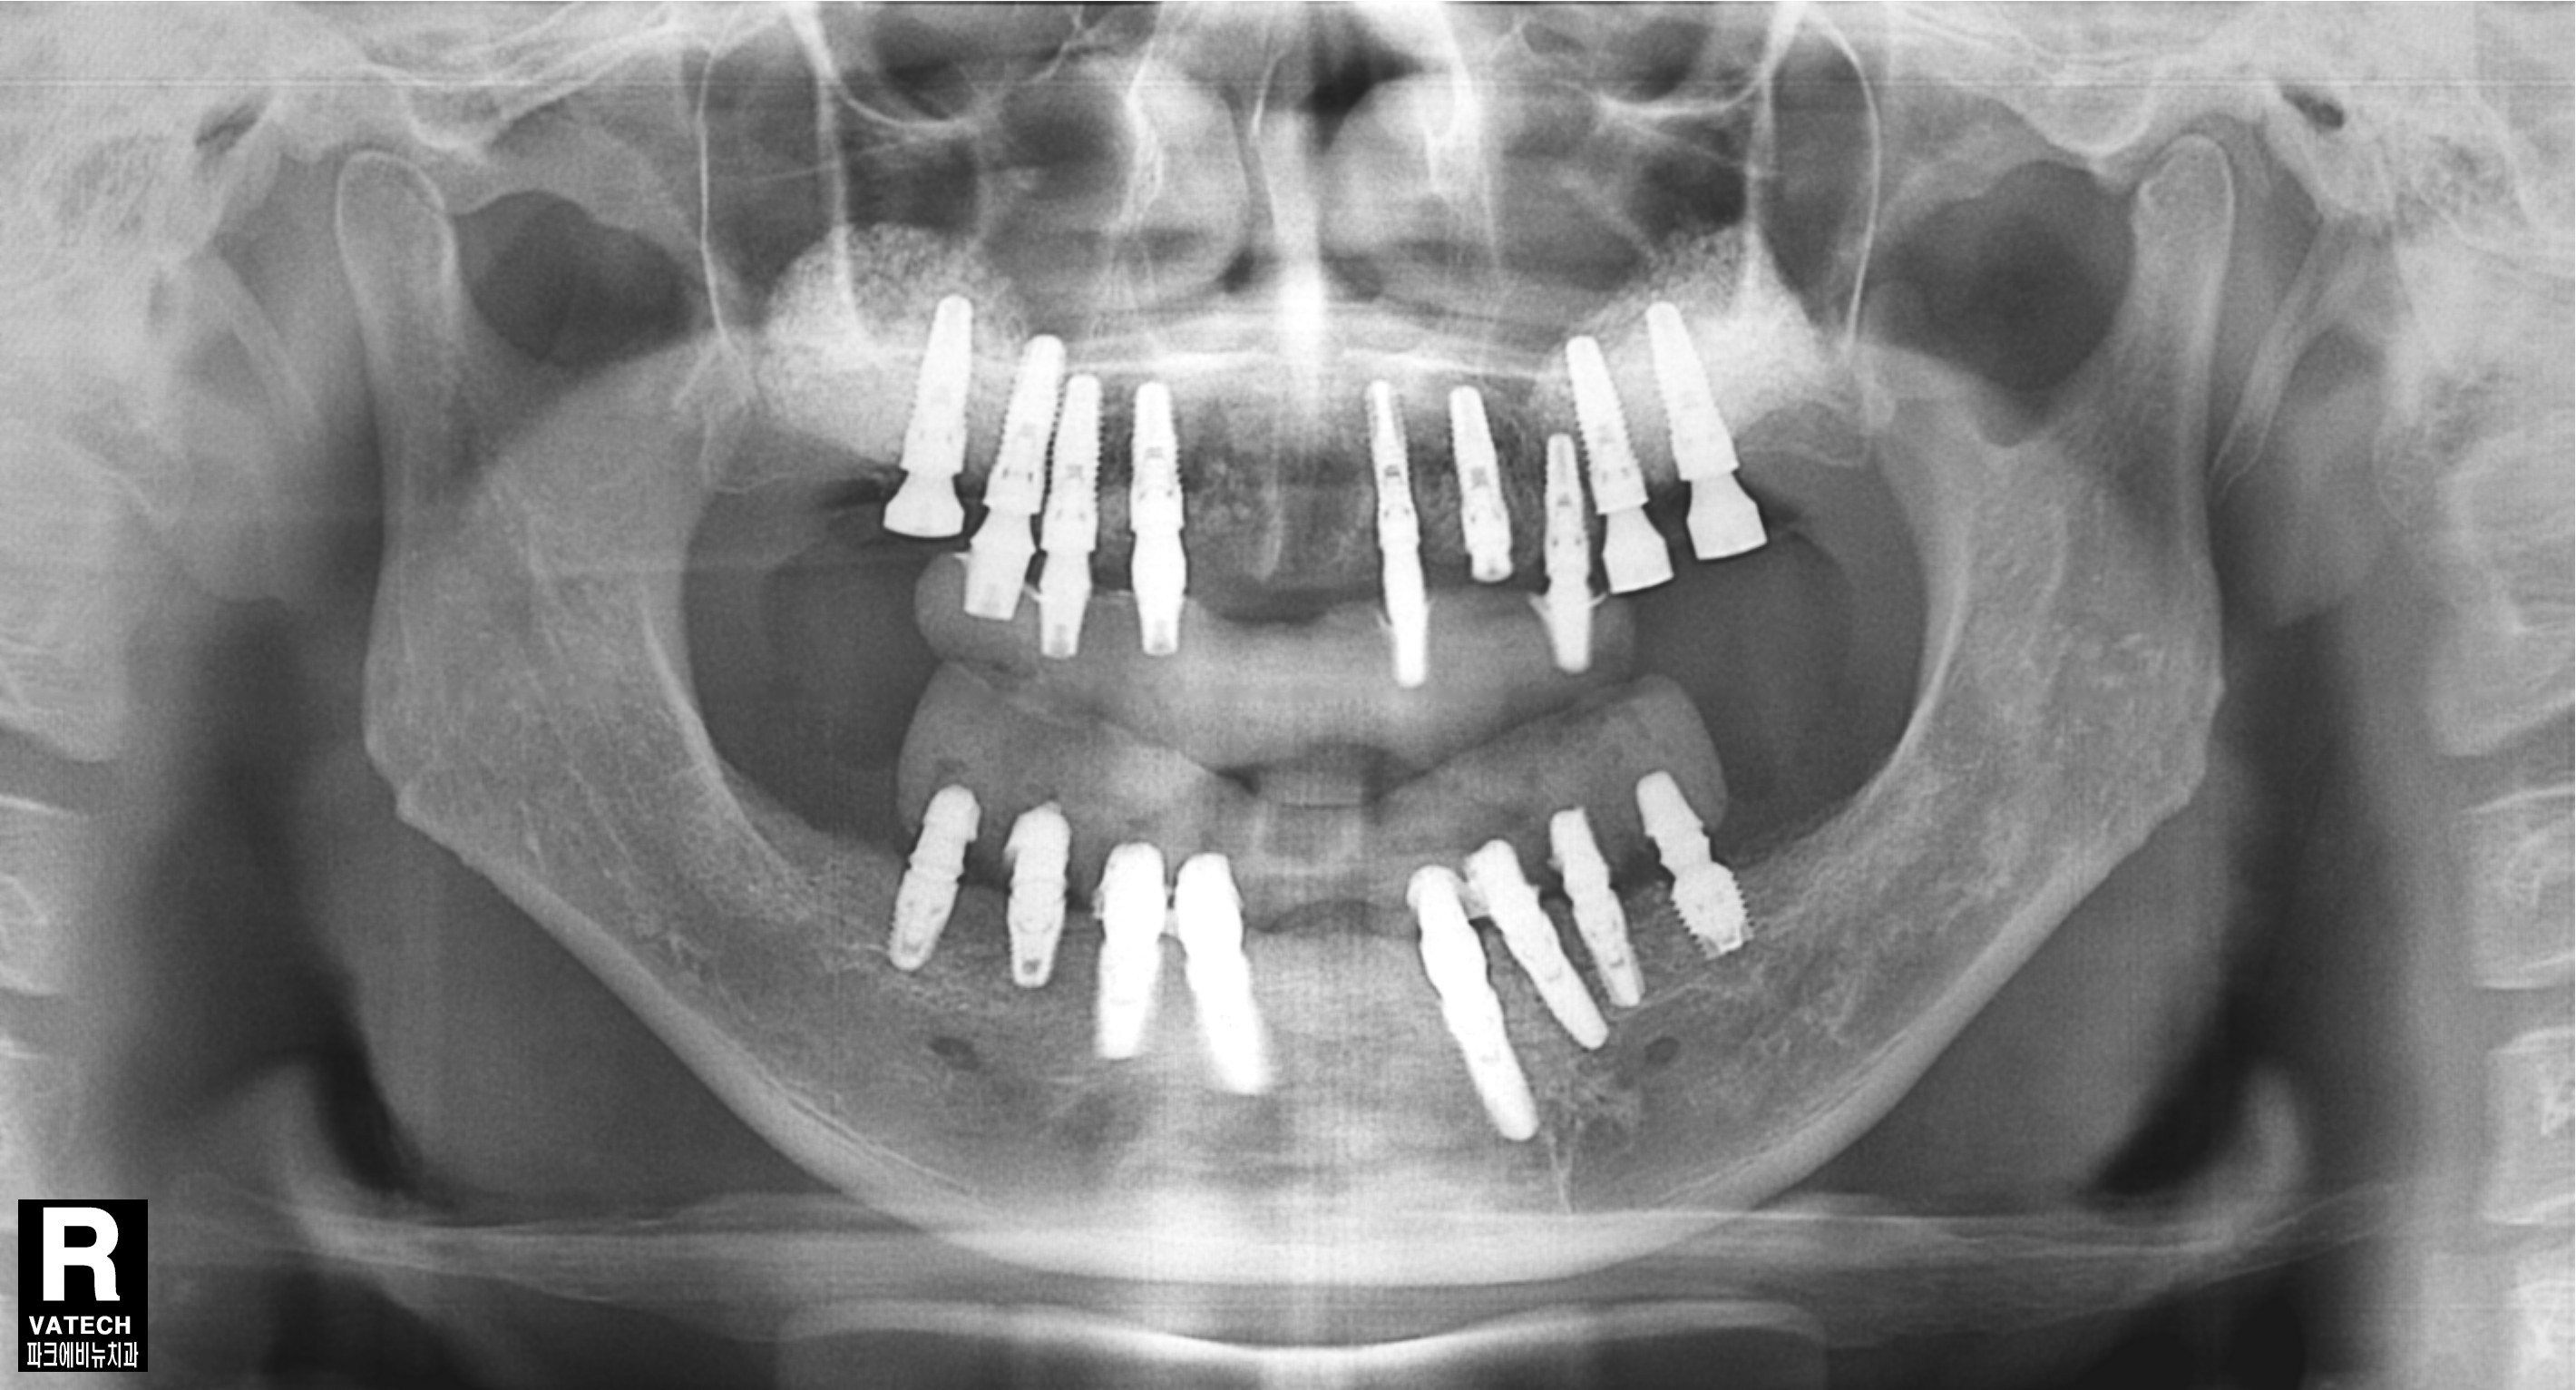

파노라마 방사선 사진도 살펴보면 치아를 잡는 치조골이 치아 뿌리 끝까지 많이 녹았음 확인할 수 있었습니다.

따라서 치아를 발치하고 전악 임플란트를 수복하기로 결정 하였습니다.

치료 중 찍은 방사선 사진입니다.

치료 필요에 따라 뼈이식도 진행하였습니다.